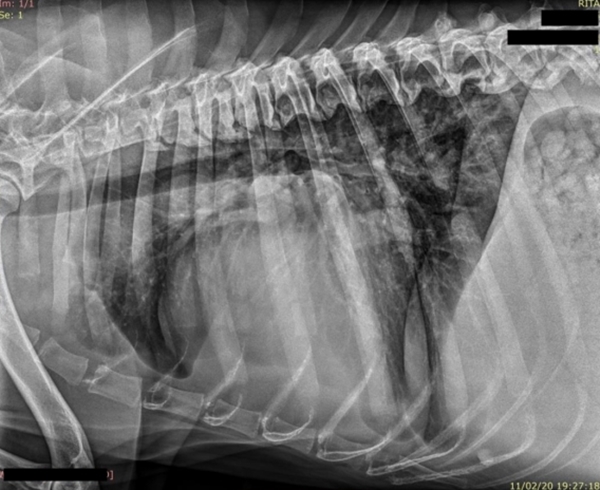

Tras el proceso de estabilizar el distrés respiratorio que presentaba, se realiza estudio radiográfico del tórax

Y se recomienda:

- Revaluar estudio radiográfico tórax.